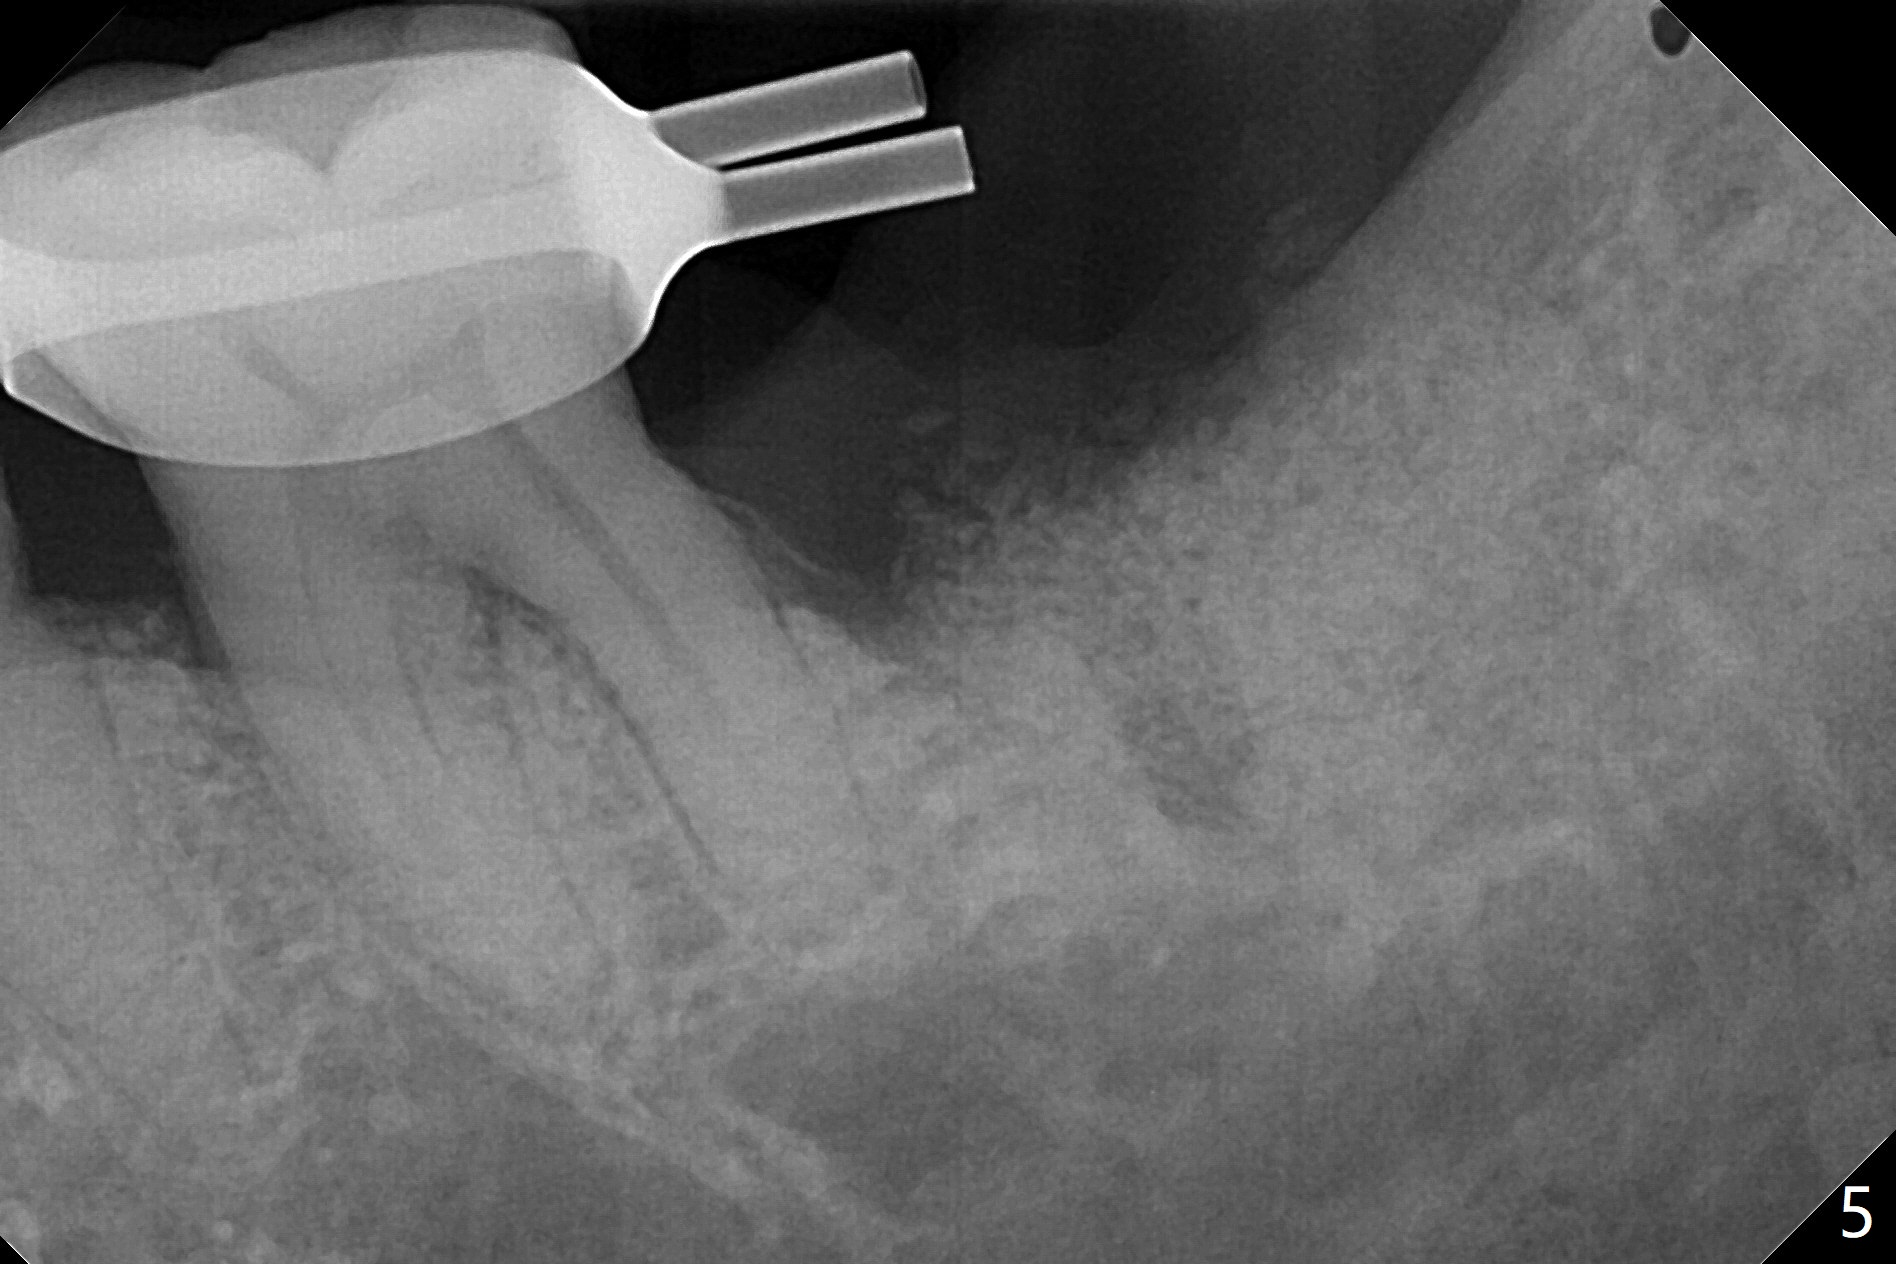

病人回来左下7拔牙植牙,十分感激导板取模后松动牙固位(图一),让他能正常吃饭。去除颊侧树脂和钢丝,6,7之间树脂自动脱落。拔牙后,肉芽组织很多,需要把局麻药注射至肉芽组织中,刮除时不慎远中舌侧牙龈穿孔。尽管纱布压迫,渗血相当多。怀疑导板就位不全,没有纠正。完成钻洞,报废植体无法就位。放置最后一个钻头,根尖片显示钻洞太浅了(图二)。再次磨除6颊侧,远中树脂,导板好像就位,重复钻洞,仍旧太浅(图三),CT表明钻洞偏颊侧(图四)。准备徒手改变钻洞,但是病人疼痛,只好植骨(粘性骨粉)(图五),牙槽窝舌侧,咬合面各覆盖一张PRF膜(图六:箭头),牙间隙维持器和牙周敷料固定。导板在曾经有树脂地方必须缓冲(图七:6;八:*,与图一对比),磨除深度有时不准确。术后两周牙周敷料仍稳定(图九),虽然病人希望撤除,我们偏向保留。反正病人正在做局部牙齿矫正。术后三周牙周敷料脱落,左上6咬合面树脂为了对侧局部牙齿矫正(图十)。骨粉有些丧失(图十一),最好手术时使用不可吸收膜。术后四个月牙槽窝充满骨粉,可以在下齿槽管颊侧植入4x8.5毫米植体(图十二)。